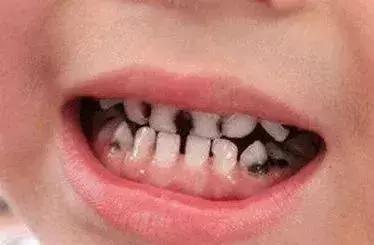

十岁儿子长了龋齿,妈妈没当回事,认为乳牙发生龋齿以后长出恒牙就好了,结果问题越来越严重!

医生在和孩子母亲交流过程中得知,原来这个孩子从小喜欢吃甜食,小的时候牙齿就有龋齿,4岁的时候,曾经带他到医院诊治过,因为孩子小不配合治疗,

妈妈又听人家说乳牙龋齿不用治疗,换了恒牙就好了,也就一直没在意。

乳牙龋齿,如果不及时治疗的话,会影响恒牙的发育和萌发,甚至会影响孩子的正常发音。

像这个患者的儿子那样,因为乳牙龋齿没有及时治疗,导致乳牙严重龋坏而新生恒牙在没有完全发育好的情况下过早萌出,恒牙又没有得到很好的保护,而导致恒牙也发生龋齿的恶性循环。